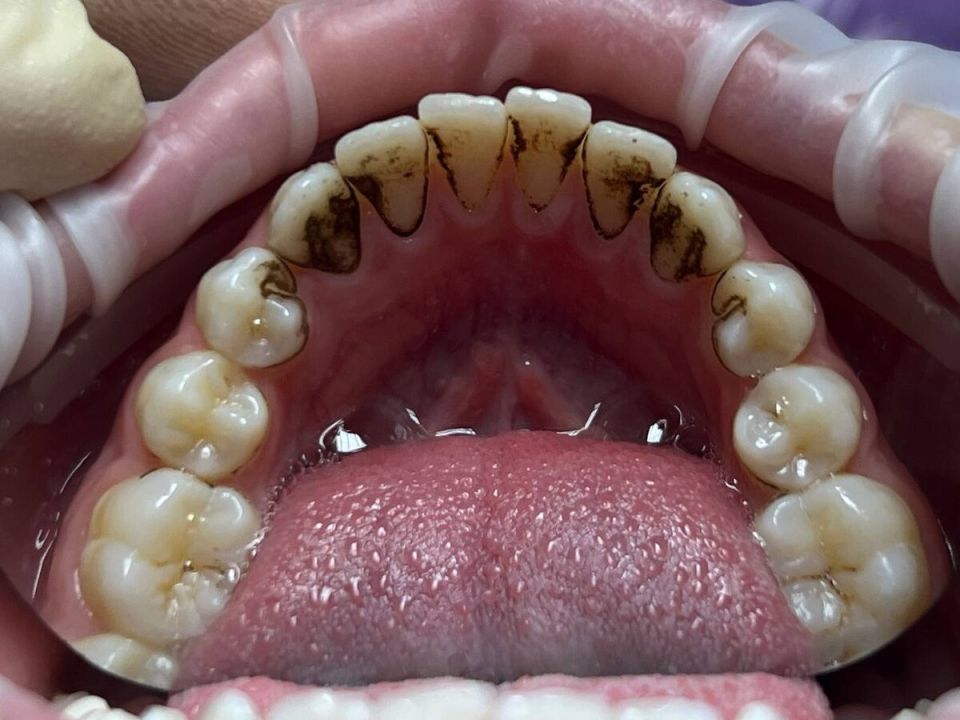

Налет Присли — это особый вид зубного налета, который чаще всего наблюдается у детей. Он обладает характерными признаками:

• Плотная текстура и темный цвет, варьирующий от коричневого до глубокого черного;

• Образование в пришеечной области, вдоль линии десен или на внешних поверхностях зубов;

• Сложности с удалением с помощью обычной зубной пасты и щетки;

• Хоть зубы могут оставаться абсолютно здоровыми, эстетический дискомфорт от налета ощущается.